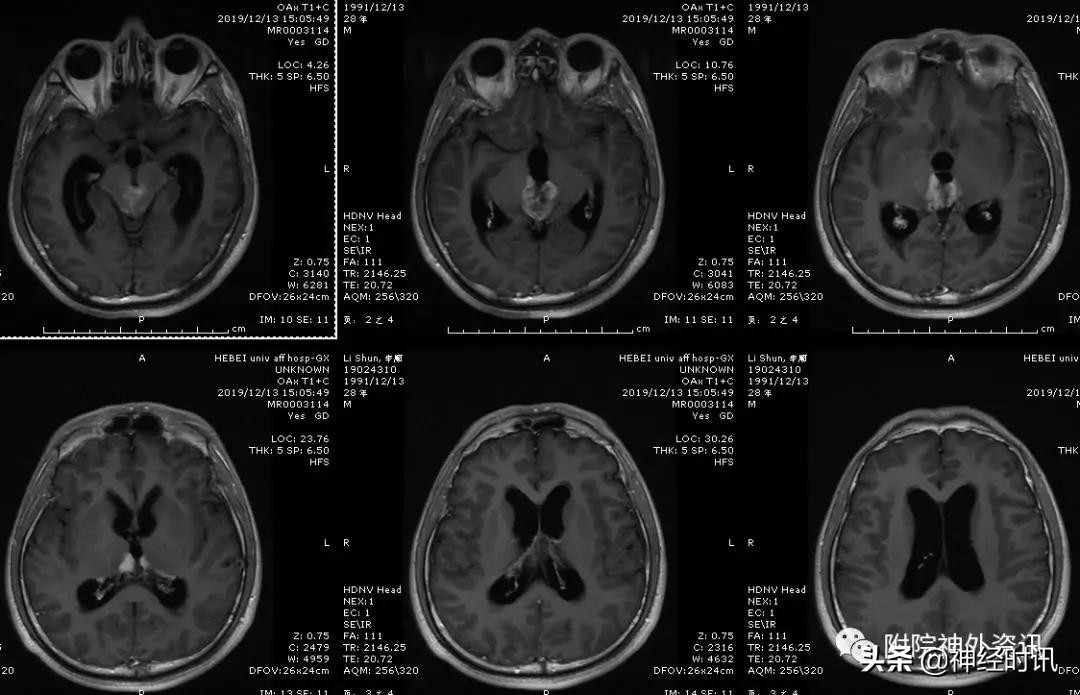

松果体区肿瘤影像表现各式各样,部分影像特征能鉴别出一些肿瘤性质。高分辨率的MRI能鉴别出肿瘤是来源于松果体还是附属结构。

生殖细胞瘤强化明显,边界清楚,沿着第三脑室侧壁生长,形成所谓的“蝶形征”。

脑膜瘤增强扫描后表现为均一明显强化的实质性肿瘤,MRI特征性的表现是与大脑镰、小脑幕的关系密切,周边硬膜有增厚。血清学检查含有生殖细胞源性细胞的肿瘤可有HCG及AFP的升高。

诊断过程中很重要的就是MRI及CT检査,高分辨率的MRI可以显示肿瘤的一些特征表现,帮助判断肿瘤的大致病理性质。生殖细胞瘤、畸胎瘤、绒毛膜癌、松果体实质肿瘤及脑膜瘤有一定的特征性表现。但影像学检査许多特征性的表现可以交叉岀现在几种病理性质及治疗方案完全不同的肿瘤中,且敏感性不高,目前的影像学检查更重要的作用是明确肿瘤的大小、血供情况、肿瘤主要扩展的方向、质地、位置及周围组织的关系来确定手术入路和手术难点。

男性,28岁,主因复视20余天入院,查体双瞳孔不等大,直径左=3. 5mm,右=3.0 mm,对光反射迟钝,双眼上视困难,左眼眼位异常,向内下斜视。